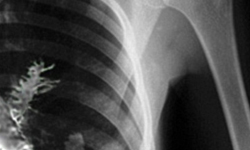

苦主就是這位青年Artyom Sidorkin先生,事發當時他28歲,身體不舒服經常咳血,於是到了醫院照X光檢查後,醫生研判是腫瘤。

(好詭異的腫瘤)

醫生研判應該是Sidorkin把松樹種子吸進肺裡,種子在溫暖的肺裡發芽成長,針葉甚至戳破了Sidorkin的肺部,引發咳嗽甚至出血。

令人感到相當奇異的是,松樹種子居然能夠在人的身體裡繁殖,而不是在不適應的環境中默默敗壞死亡。它跟環境奮鬥而重生,甚至出現在X光照片上,證明它即使沒有土壤也活得好好的,實在令人驚奇。不過今後大家呼吸的時候要更小心了喔……